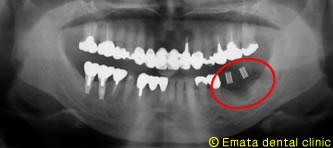

GBR治療例2

患者さんは4年前に、右奥歯を当院でインプラント治療をしまして、反対側の歯が折れている可能性があるので、治療を勧ましたが患者さんは痛くないのでこのままでいいということで、その後来院せず、去年の12月お痛みがあり救急で来院しました。

Before

レントゲンをとると歯は割れていてその周りの骨も大きく無くなっていました。患者さんはインプラントが良く噛めるので、反対側もインプラント治療を希望されました。

お痛みがでた歯の周りは黒くなり骨が無いのがおわかりですか。

これだけ、骨欠損が大きいと、グラフトレス(傾斜埋入、ショートインプラント)やスプリットクレストは難しいと思います。ブロック骨か、GBRの骨造成が適応症だと思います。